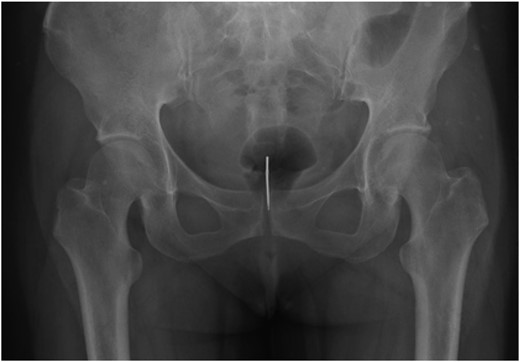

An X-ray of her pelvis showed a 3-cm radiopaque foreign body (Fig 1). The patient underwent an examination under anaesthesia and a diagnostic rigid cystoscopy was performed which identified a 9-cm crochet needle in the bladder, with the sharp end lodged in the mucosa of the proximal urethra (Fig 2). There was evidence of debris in the bladder but no signs of bleeding or bladder wall injury or perforation. The foreign body was removed successfully with graspers and bladder washouts were undertaken to clear the debris from the bladder. The procedure and the recovery were uneventful. A psychiatric consultation was recommended, but the patient refused. She was discharged on the following day and she was prescribed oral antibiotics for 5 days. Unfortunately, the patient failed to attend the follow-up appointment.